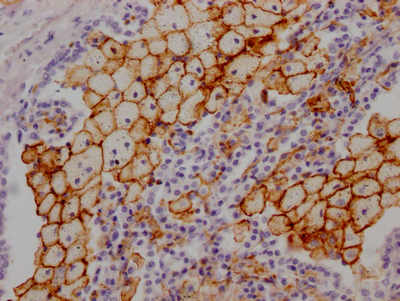

IHC image of CSB-RA268157A0HU diluted at 1:100 and staining in paraffin-embedded human lung tissue performed on a Leica BondTM system. After dewaxing and hydration, antigen retrieval was mediated by high pressure in a citrate buffer (pH 6.0). Section was blocked with 10% normal goat serum 30min at RT. Then primary antibody (1% BSA) was incubated at 4℃ overnight. The primary is detected by a Goat anti-rabbit IgG polymer labeled by HRP and visualized using 0.05% DAB.